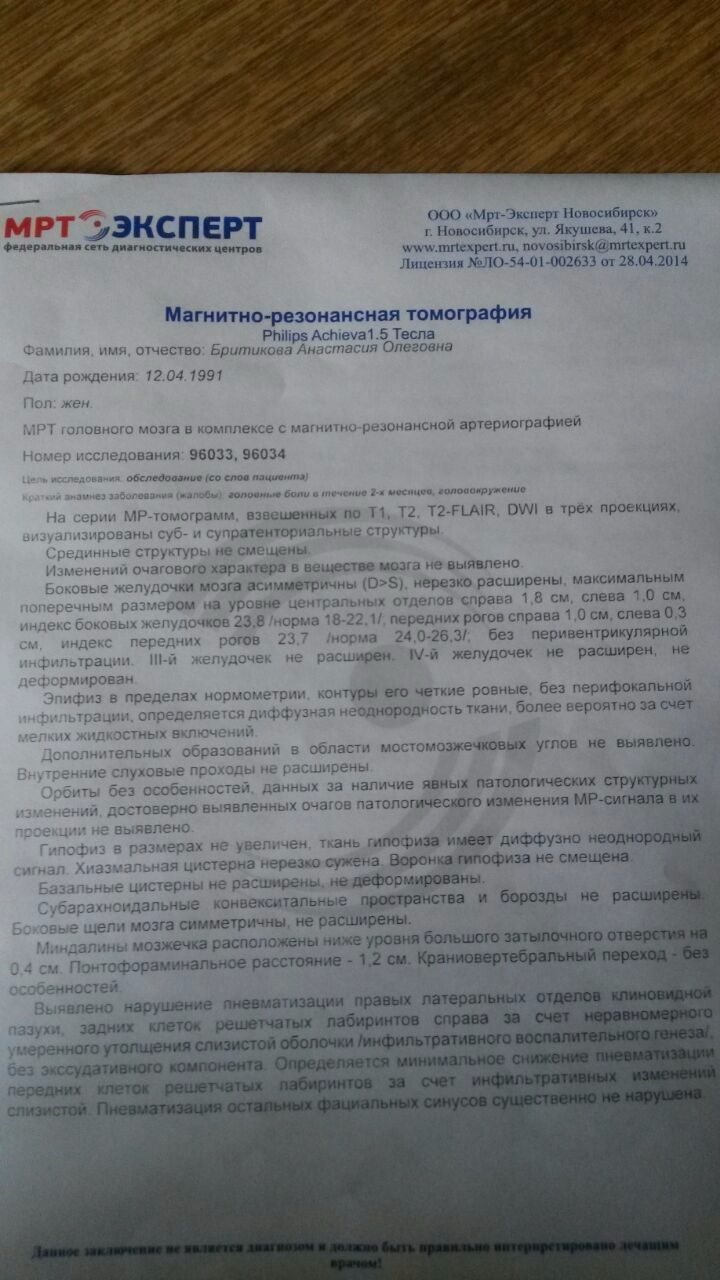

МРТ головного мозга: Расшифровка снимков и Интерпретация

Раздел: Визуальные уроки